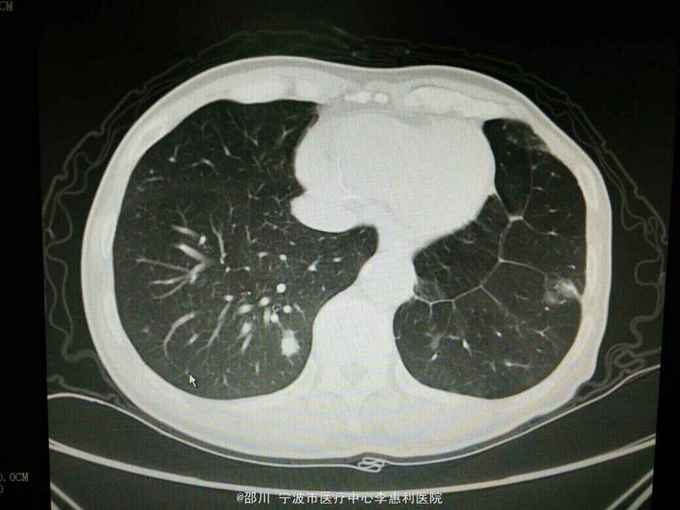

患者男,69岁。左上肺腺癌术后3年余,因“咳嗽咳痰半月余”入院。 病史: 3年余前无明显诱因出现咳嗽,少量白痰,无咯血,无胸痛,至上海某医院就诊,诊断为“左肺阴影:肺癌?”,于2012-5-17全麻下行“左肺上叶切除术”,术后病理提示“肺腺癌”,随后予2012-6-26和2012-8-2在宁波某医院行化疗2个周期(培美曲塞针0.8d1, 卡铂针0.4d1) , 以后定期复查胸部CT和血肿瘤标志物,未发现明显肿瘤复发征象。2015-4-23患者在我院查胸部CT提示“左肺多发炎症样高密度影,右肺多发结节”。半月余前患者出现咳嗽,有少量白痰,无发热,无胸闷气促,2015-10-30我院复查胸部CT提示“左肺弥漫性高密度影,右肺散在多发结节,较4-23片范围,大小均增大”。 既往有“高血压病”史3年,平时规律服用药物治疗,血压控制良好。否认其他疾病史。 个人史,婚育史,家族史无殊。 2015-4-23我院胸部CT见下图。